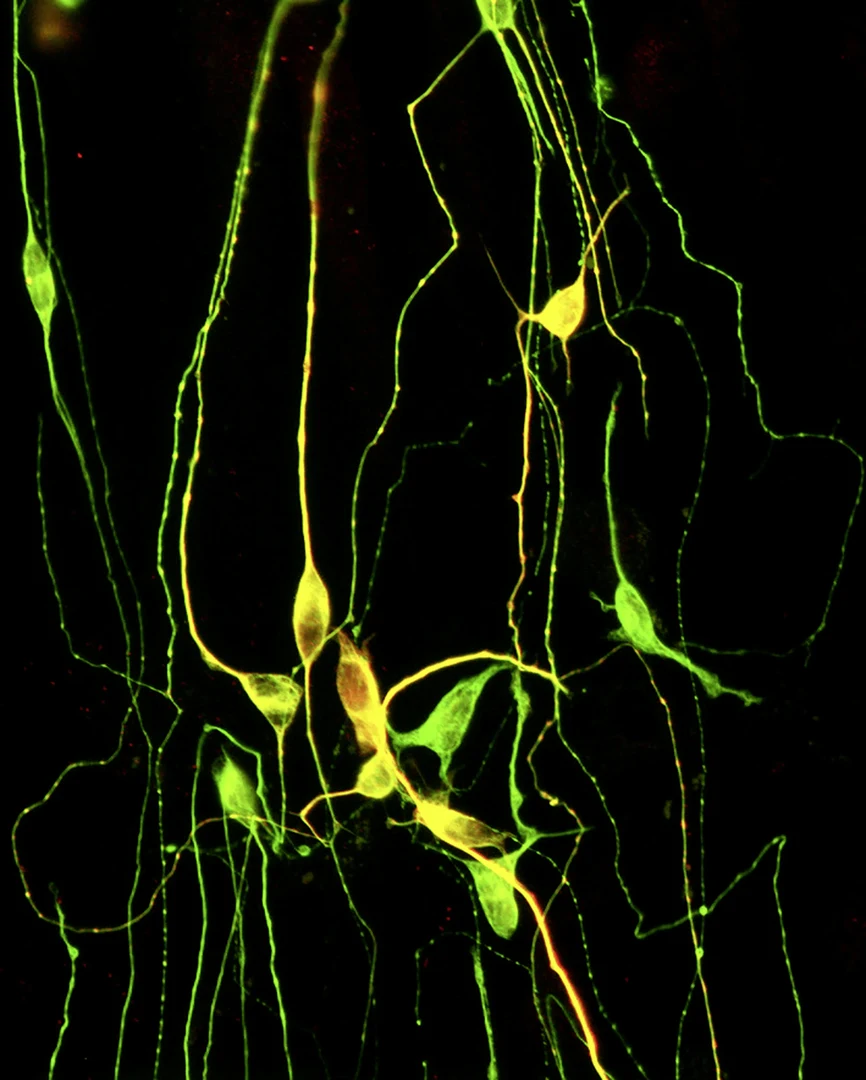

Nervenzellen, die direkt aus Hautzellen gewonnen wurden:

Nervenzellen, die direkt aus Hautzellen gewonnen wurden: - Sie sind mit Antikörpern gegen die neuronalen Proteine ßIII-Tubulin (grün) und MAP2 (rot) gefärbt. © Julia Ladewig/Uni Bonn